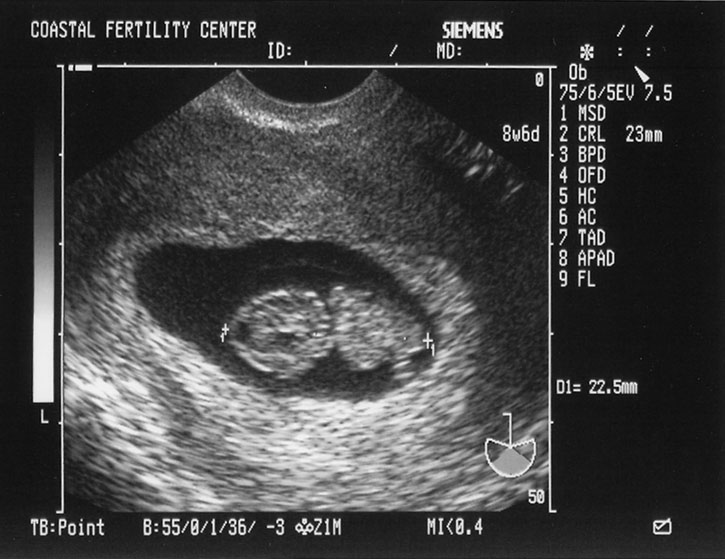

5/17/05 Baby B - 8w6d